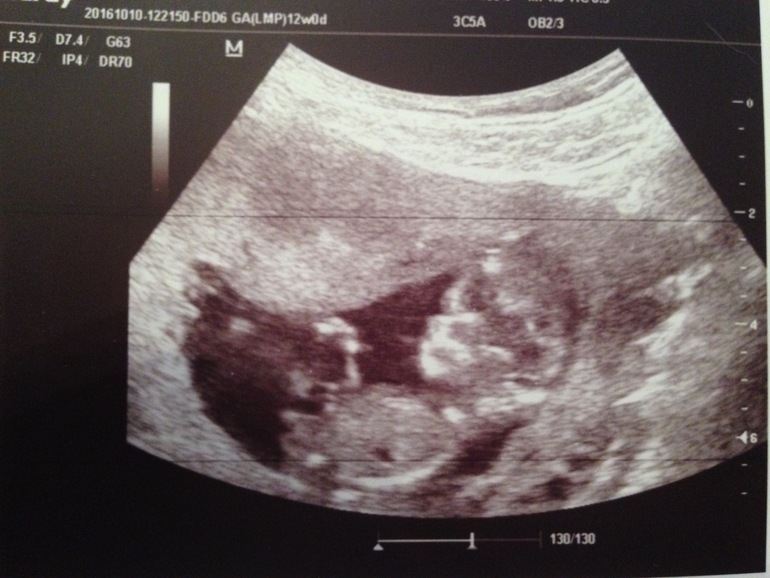

Сегодня сходила на узи посмотрела нашу крошку. Сегодня у нас 12 недель ровно, а по узи 11,5. Ничего страшного. Ктр 48 мм, ЧCC166, все остальные параметры в норме. Вообще прослезилась когда сердечко включили, волновалась как первый раз. Слава богу все хорошо. Всем счастья

И фото малыша снятое мною на телефон